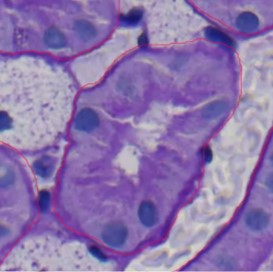

The annotations produced by the AI model show excellent quality in this close-up photograph. The red lines closely adhere to the cellular structure limits, demonstrating a high degree of precision in identifying the cell borders. It is well aligned with the natural curves, and it seems to have delineated every visible structure, indicating thorough detection. Reliability is ensured by the uniform annotation style, which defines each cell in a comparable way. Thin red lines are used without obscuring interior features to retain clarity. The annotations are detailed, paying close attention to the minute features of the cell borders, suggesting that the model can accurately represent complex changes in cell shapes. All in all, the annotations are precise, comprehensive, coherent, unambiguous, and targeted.

In this you will see a great annotation that AI did and its annotate the whole object and separated with another one and the quality is so good in here, the AI exclude the nuclei from the left object.

quality of but in some where you will see that the separations between two object it’s no complete as you can see in the image in bellow but also they annotated the objet really good they exclude the nuclei and annotated all mainframe and sharing Mein brane between tubuli and peri tubuli capilari (PTC).